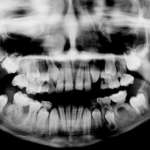

Le manifestazioni sindromiche del cavo orale come diagnosi nella crescita del paziente

Diverse sindromi presentano manifestazioni a livello orale che spesso anticipano quelle sistemiche. Fra queste, la displasia immuno-ossea di Schimke, la cui diagnosi precoce e relativo inquadramento terapeutico possono risultare determinanti sulla prognosi del paziente.